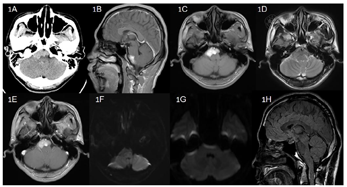

头颅CT平扫:右侧桥小脑角区,脑桥及延髓腹侧高密度占位,无钙化(CT值为48-63HU)。

头颅MRI平扫增强以及弥散加权成像:右侧桥小脑角区,脑桥及延髓腹侧短T1以及稍短T2信号,边界清晰,呈匍匐样生长,最大截面约3.2cm×1.8cm×2.3cm,脑桥延髓稍受压,四脑室受压,增强扫描未见肿瘤明显强化;弥散加权成像提示肿瘤信号和脑脊液相比,呈稍高信号,考虑胆脂瘤(图1A-F)。

治愈。患者术后予以抗感染,营养支持等对症处理后,患者顺利出院,出院时患者无头痛、头晕,体温正常,无面瘫,双耳听力同术前,无声音嘶哑以及饮水呛咳等后组颅神经症状;患者切口愈合良好。随访过程中,头痛头晕症状消失,无再发继发性三叉神经痛。患者术后3个月复查头颅MRI平扫以及弥散加权成像提示肿瘤全切,无复发,四脑室及脑干受压解除(图1G~H)。